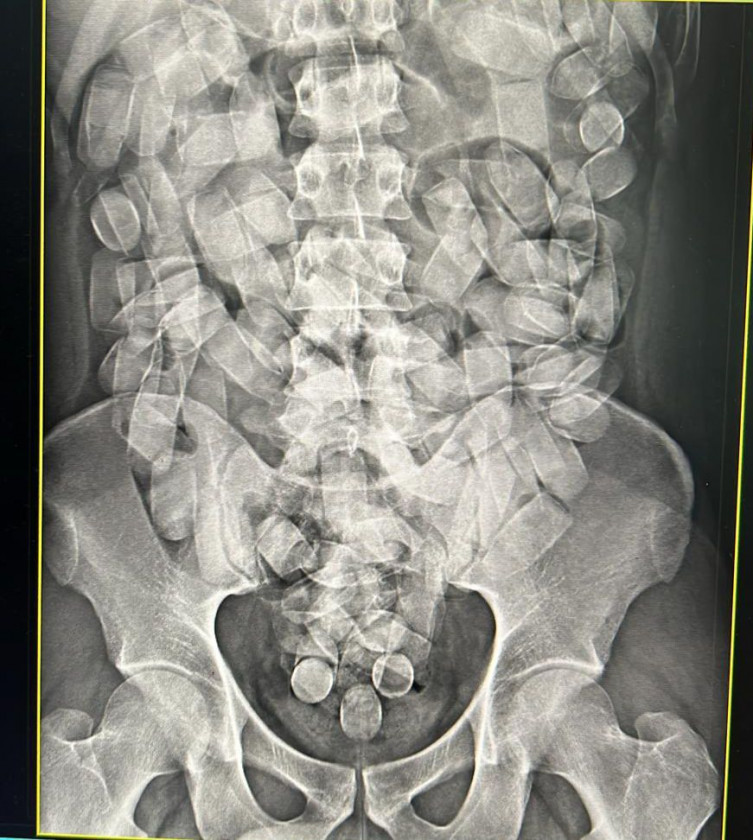

Ele seguiria para São Paulo, mas acabou despertando a desconfiança dos agentes. Raio-x confirmou que ele havia ingerido a droga. O homem disse que engoliu 125 cápsulas e foi levado para a Santa Casa para expelir a droga.

Divulgação/PF

Homem foi levado ao hospital para expelir as cápsulasApós isso, será levado para a Delegacia da PF para o registro da prisão em flagrante. Em caso de condenação judicial, a pena varia de 5 a 15 anos de reclusão.